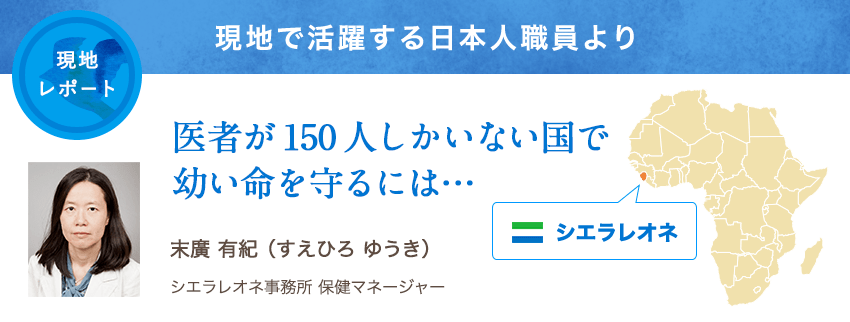

私が勤務するシエラレオネは、アフリカ大陸の西端に位置する、世界で最も貧しい国のひとつです。2002年に内戦が終結したあとも、エボラ出血熱の流行や自然災害など度重なる危機の影響で復興が遅れ、国民の大半がいまだ安全な水も電気も容易に利用できない生活を送っています。乳幼児の死亡率は世界で4番目に高く、マラリアをはじめ肺炎、下痢など治る病気で多くの幼い命が失われています。こうした子どもたちの命と健康を守る支援活動を策定・実施すること、それが私の仕事です。

9人に1人が5歳まで生きられない

子どもたちが病気で命を落とす大きな要因は、この国の医療人材の極端な不足です。医者の数は全国でわずか150人足らず。住民5万人強に対し1人しかいない計算です。そんな中で子どもたちの健康を支えているのが、ユニセフなどの研修を受けて各地で活動する1万5,000人の地域保健員たちです。ユニセフは今、この地域保健員を国の医療制度に一層深く組み込む取り組みを保健省とともに進めています。

家庭訪問中の地域保健員

これにより、すべての地域保健員が正当な待遇を受け、実証済みの救命方法を身につけ、医薬品を携えて、より多くの命を守れるようになってきています。今後は、最も脆弱な新生児のための医療ケアや、母子への医療無償化政策の後押しなどにも力を入れ、現在の高い乳幼児死亡率を数年以内に大幅削減することを目指しています。

明るく前向きな現地の人々といるとつい忘れそうになりますが、この国の日常生活は困窮を極めています。入院治療を終えた子どもが、自宅に戻ったとたん再び栄養不良や病気に陥るケースを目の当たりにするたび、医療だけでなく貧困・栄養・衛生・教育など多くの課題を、現地政府や他機関と力を合わせて解決していくことの重要性を痛感します。一人でも多くの子どもが健康で幸せな人生の一歩を踏み出せるよう、私も力を尽くします。